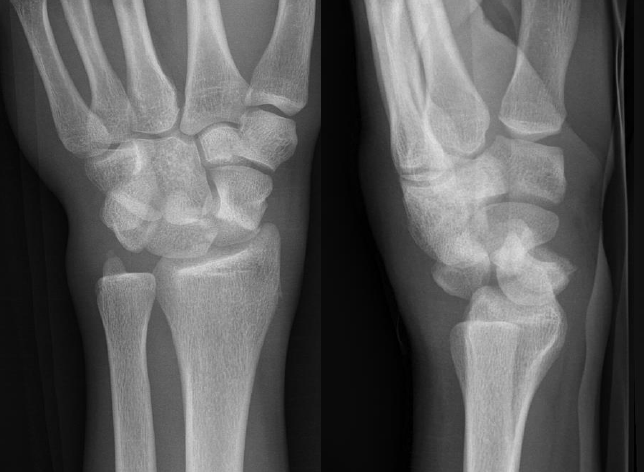

AP X-ray

Disruption of Gilula's 3 smooth carpal arcs / triangular lunate

Normal versus disruputed Gilula's carpal arcs

Piece of pie / triangular appearance of lunate

Lateral xray

Distal radius / lunate / capitate: not aligned, spilled teacup

Normal versus spilled tea cup appearance on lateral with spilled tea cup